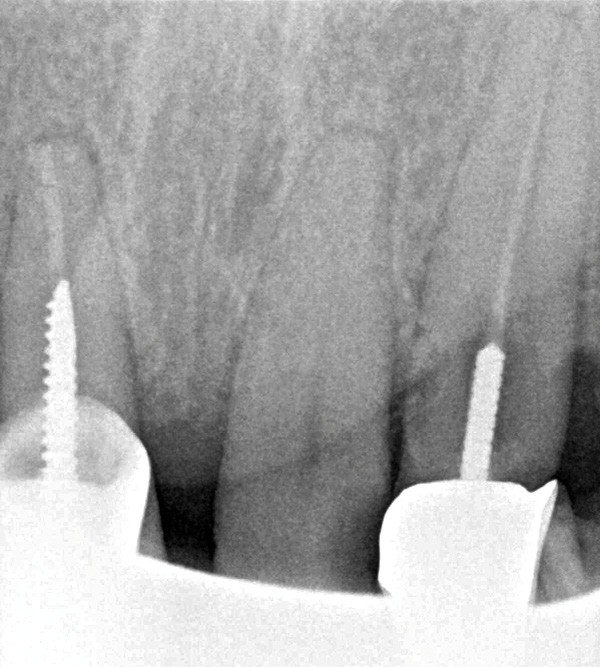

Un patient de 84 ans, en bon état de santé générale, consulte pour la perte de trois couronnes solidarisées métalliques 17, 16 et 15 qui permettaient la rétention d’une PAP à châssis métallique (fig. 1 à 5).

L’examen clinique permet de mettre en exergue, au maxillaire :

– 17, 16 sont à l’état de racines, 15 est déjà préparée et ne présente aucune symptomatologie pulpaire ;

– 13 est intacte ;

– 12 est couronnée et présente une mobilité importante et un épaississement ligamentaire ;

– 11 est couronnée ;

– carie radiculaire importante à la 21 ;

– 22 est couronnée et présente également une carie radiculaire ;

– 13 est très cariée et présente une alvéolyse dépassant le tiers apical de la racine.